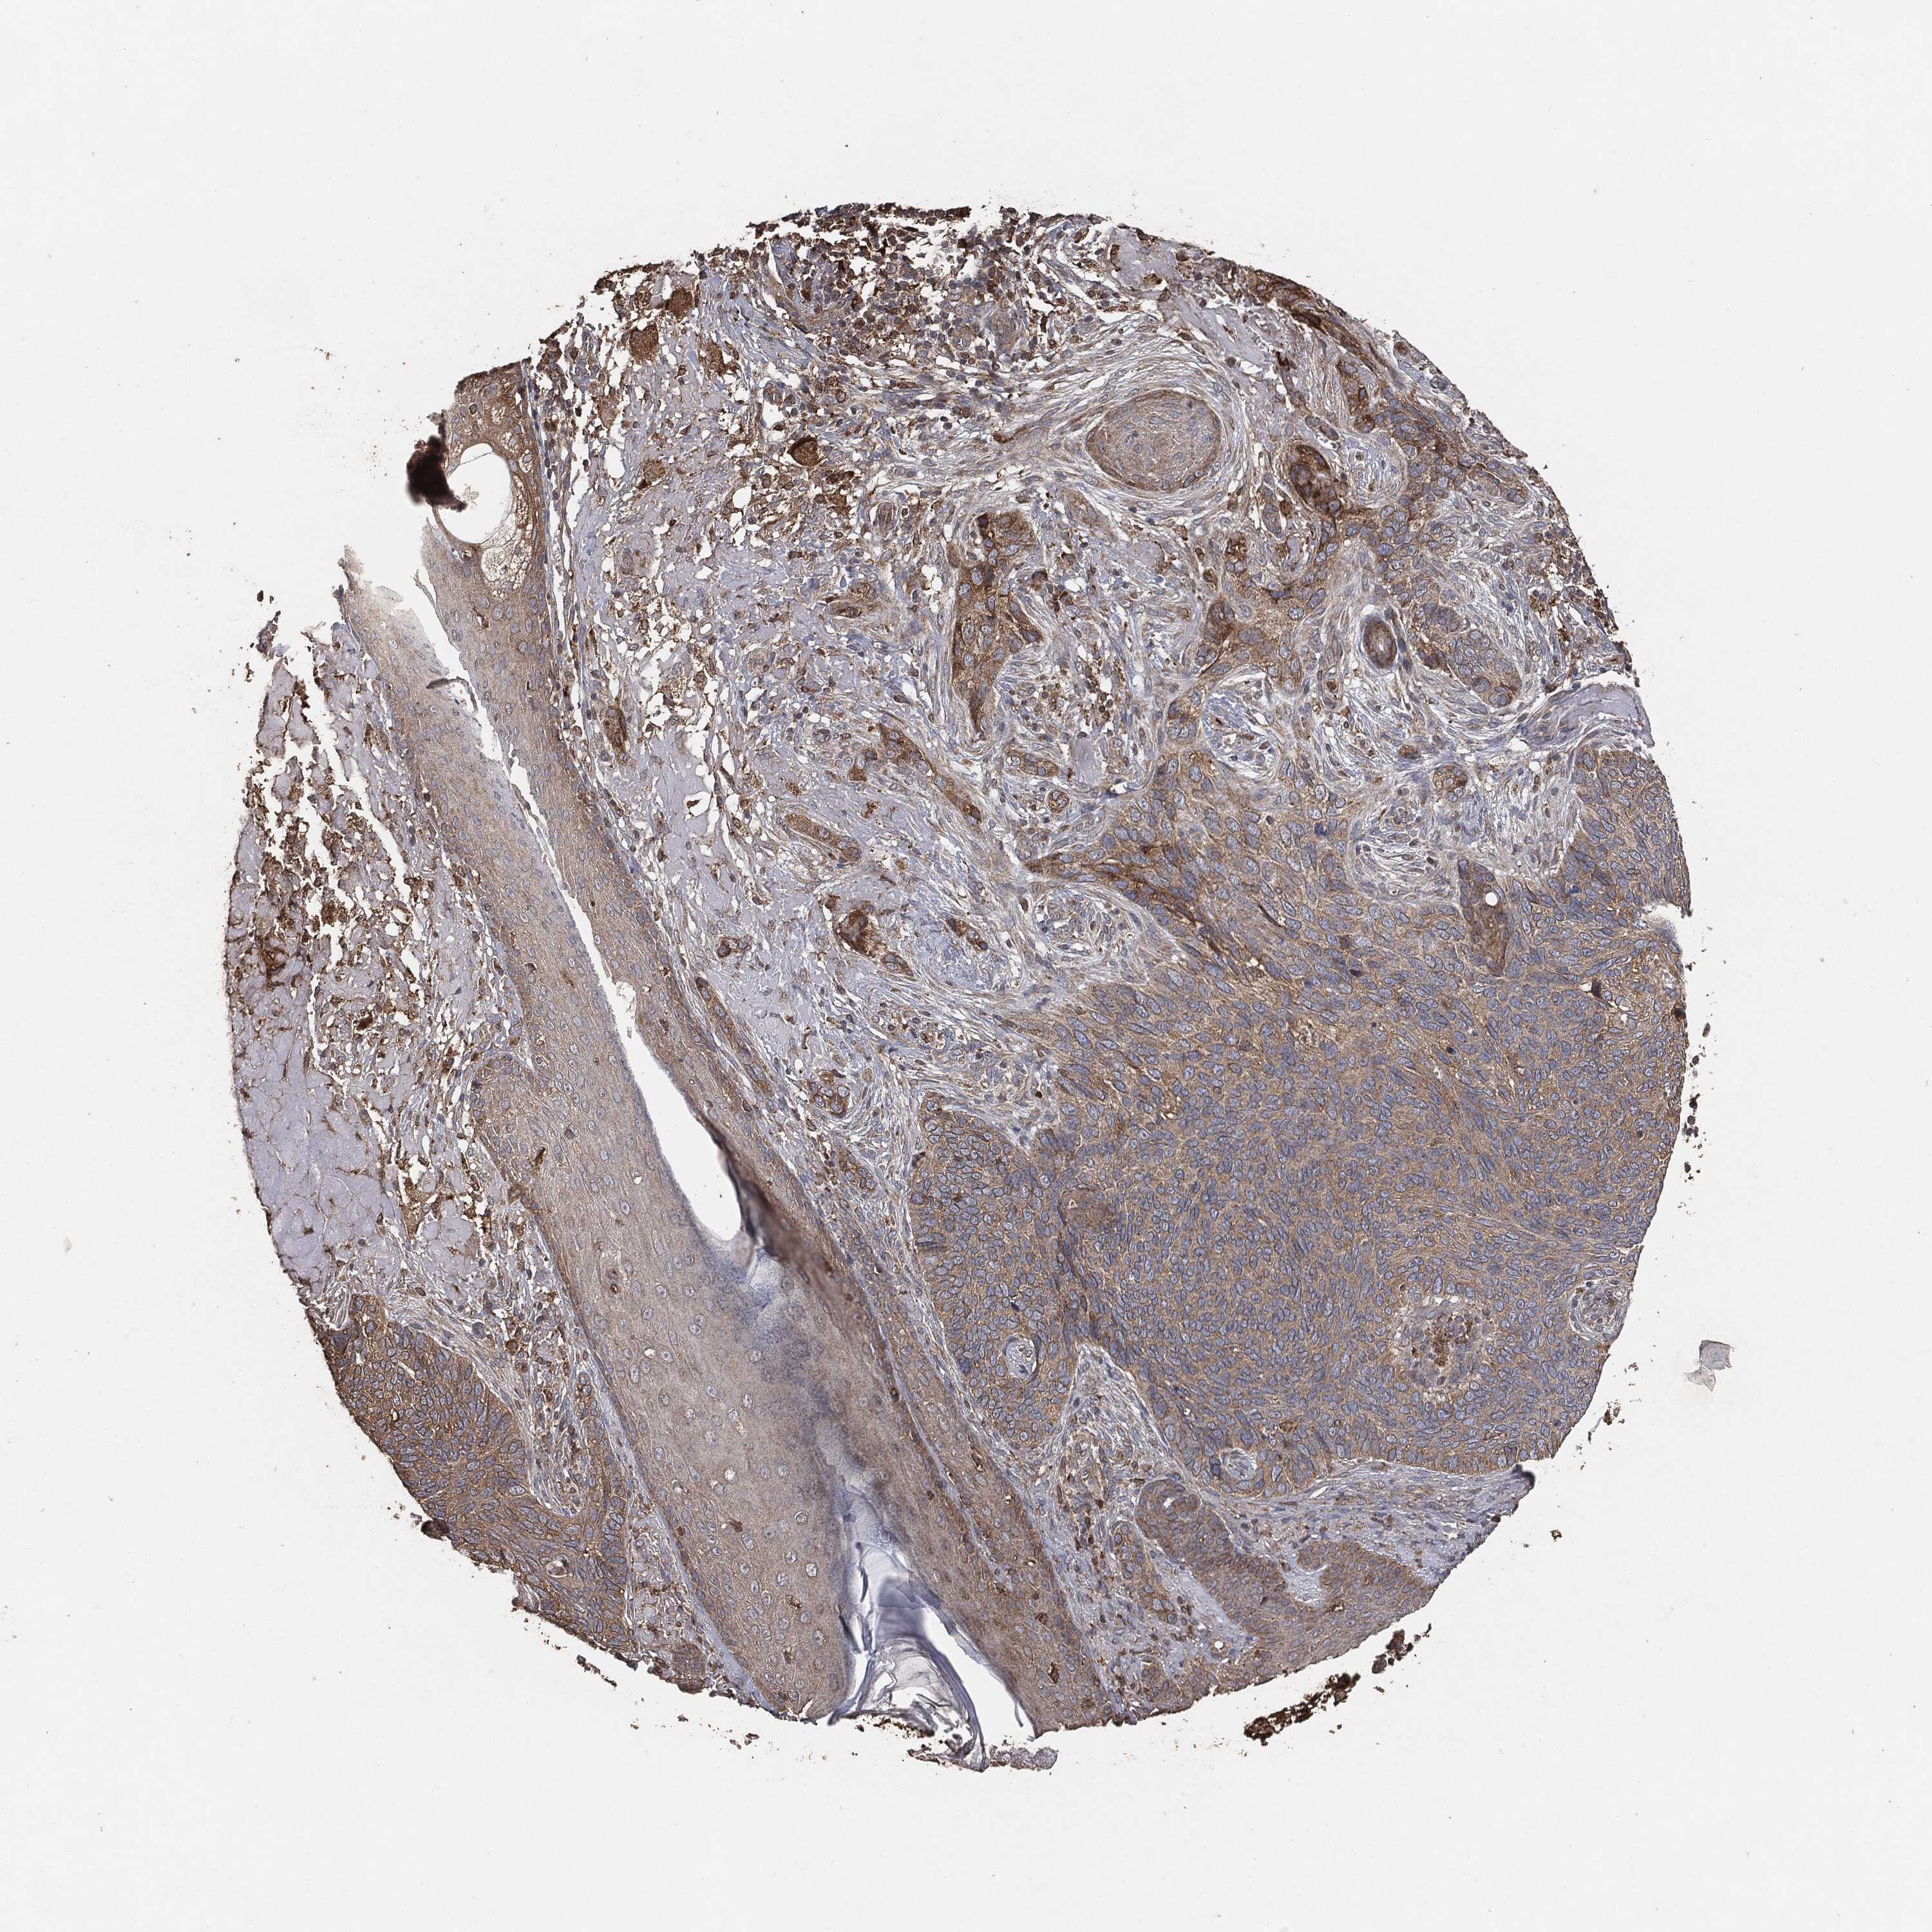

SKIN CANCER - Protein expressioni

A mouse-over function shows sample information and annotation data. Click on an image to view it in a full screen mode. Samples can be filtered based on level of antibody staining by selecting one or several of the following categories: high, medium, low and not detected. The assay and annotation is described here.

Antibody stainingi

Antibody staining in the annotated cell types in the current human tissue is reported as not detected, low, medium, or high, based on conventional immunohistochemistry profiling in selected tissues. This score is based on the combination of the staining intensity and fraction of stained cells.

Each image is clickable and will lead to virtual microscopy that enables deeper exploration of all samples and also displays staining intensity scores, fraction scores and subcellular localization as well as patient and tissue information for each sample.

Basal cell carcinoma